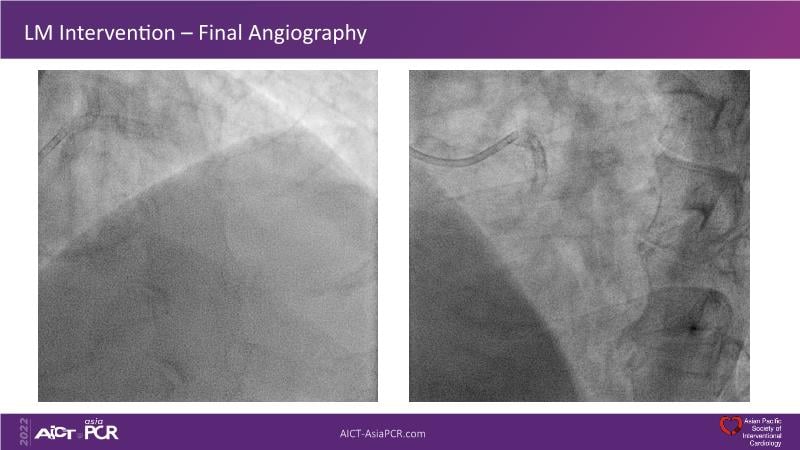

In this session, presenters describe how to use IVUS and physiology in the assessment of left anterior descending and/or left circumflex ostium in distal left main disease. Discover in the second part the general principles and clinically validated strategies for ultralow contrast coronary angiography and zero contrast percutaneous coronary intervention.

- To learn how imaging can help with strategising left main PCI, plaque preparation, device sizing and optimising results